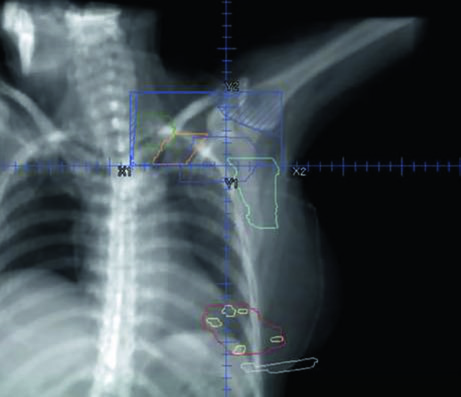

The supraclavicular field is planned separately as an anterior oblique or AP field, covering the level III and supraclavicular nodes. Figure 12.7 shows the coronal view of this field with the nodal targets overlaid — the junction between the supraclavicular field and the inferior tangents is one of the critical points of treatment, where overdose or underdose can occur if the geometry is not precise. The half-beam block technique (asymmetric jaw) minimizes divergence at the junction and reduces the risk of dose overlap.

For the tumor bed boost, an en face electron field with a custom cutout is typically used. Figure 12.8 demonstrates this setup in a 3D view: the electron field (blue) encompasses the tumor bed (maroon), surgical clips (light green), and the lumpectomy scar (gray). Electron energy selection depends on bed depth — in practice, 9–12 MeV covers most cases, following the rule that the 80% isodose reaches a depth in centimeters of approximately $E/3$, where $E$ is the energy in MeV.